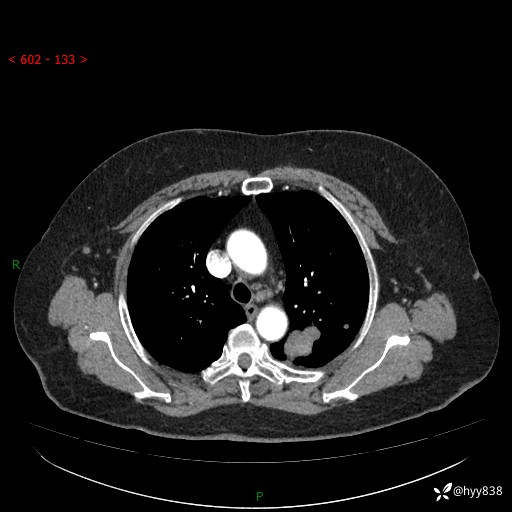

老年女性,左上肺结节8年。典型又不典型,看你如何解读---结果公布(值得分析)

主诉:检查发现左上肺结节8年,较前增大。

简要病史:患者于8年前体检行胸部CT检查发现左上肺结节(4mm),患者平素间断咳嗽咳痰,无心慌、胸闷、胸痛、呼吸困难、低热、盗汗,无头痛、头晕,无腹痛、腹胀等不适,未行特殊处理,定期复查。2023-09-21胸部CT示左上肺结节(2cm)较前增大,2024-02-01胸部CT示左上肺尖后段(39*32mm),左侧肺门及纵隔淋巴结增大,现患者欲求手术治疗,遂来我院就诊,以“左上肺结节”收入我科。 患者自起病以来,精神可,睡眠可,饮食可,大小便正常,体重无明显改变。

辅助检查:CT

胸部CT平扫

增强(动脉期+静脉期)